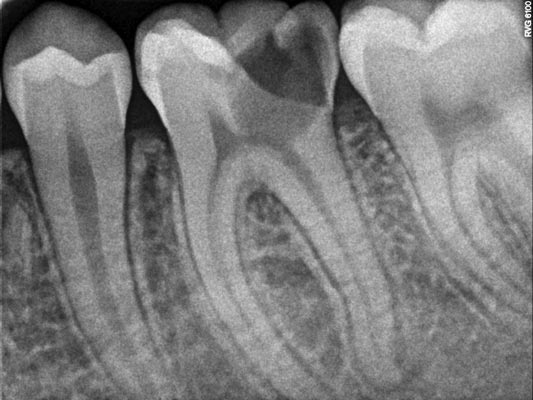

Imágenes: Endodoncia en un molar inferior izquierdo

Dado que cada diente presenta una anatomía única es fundamental identificar y tratar correctamente todos los conductos radiculares para evitar infecciones y asegurar la viabilidad del diente a largo plazo.

La endodoncia permite eliminar la pulpa dental dañada del interior del diente y de sus raíces, conservando el diente natural.